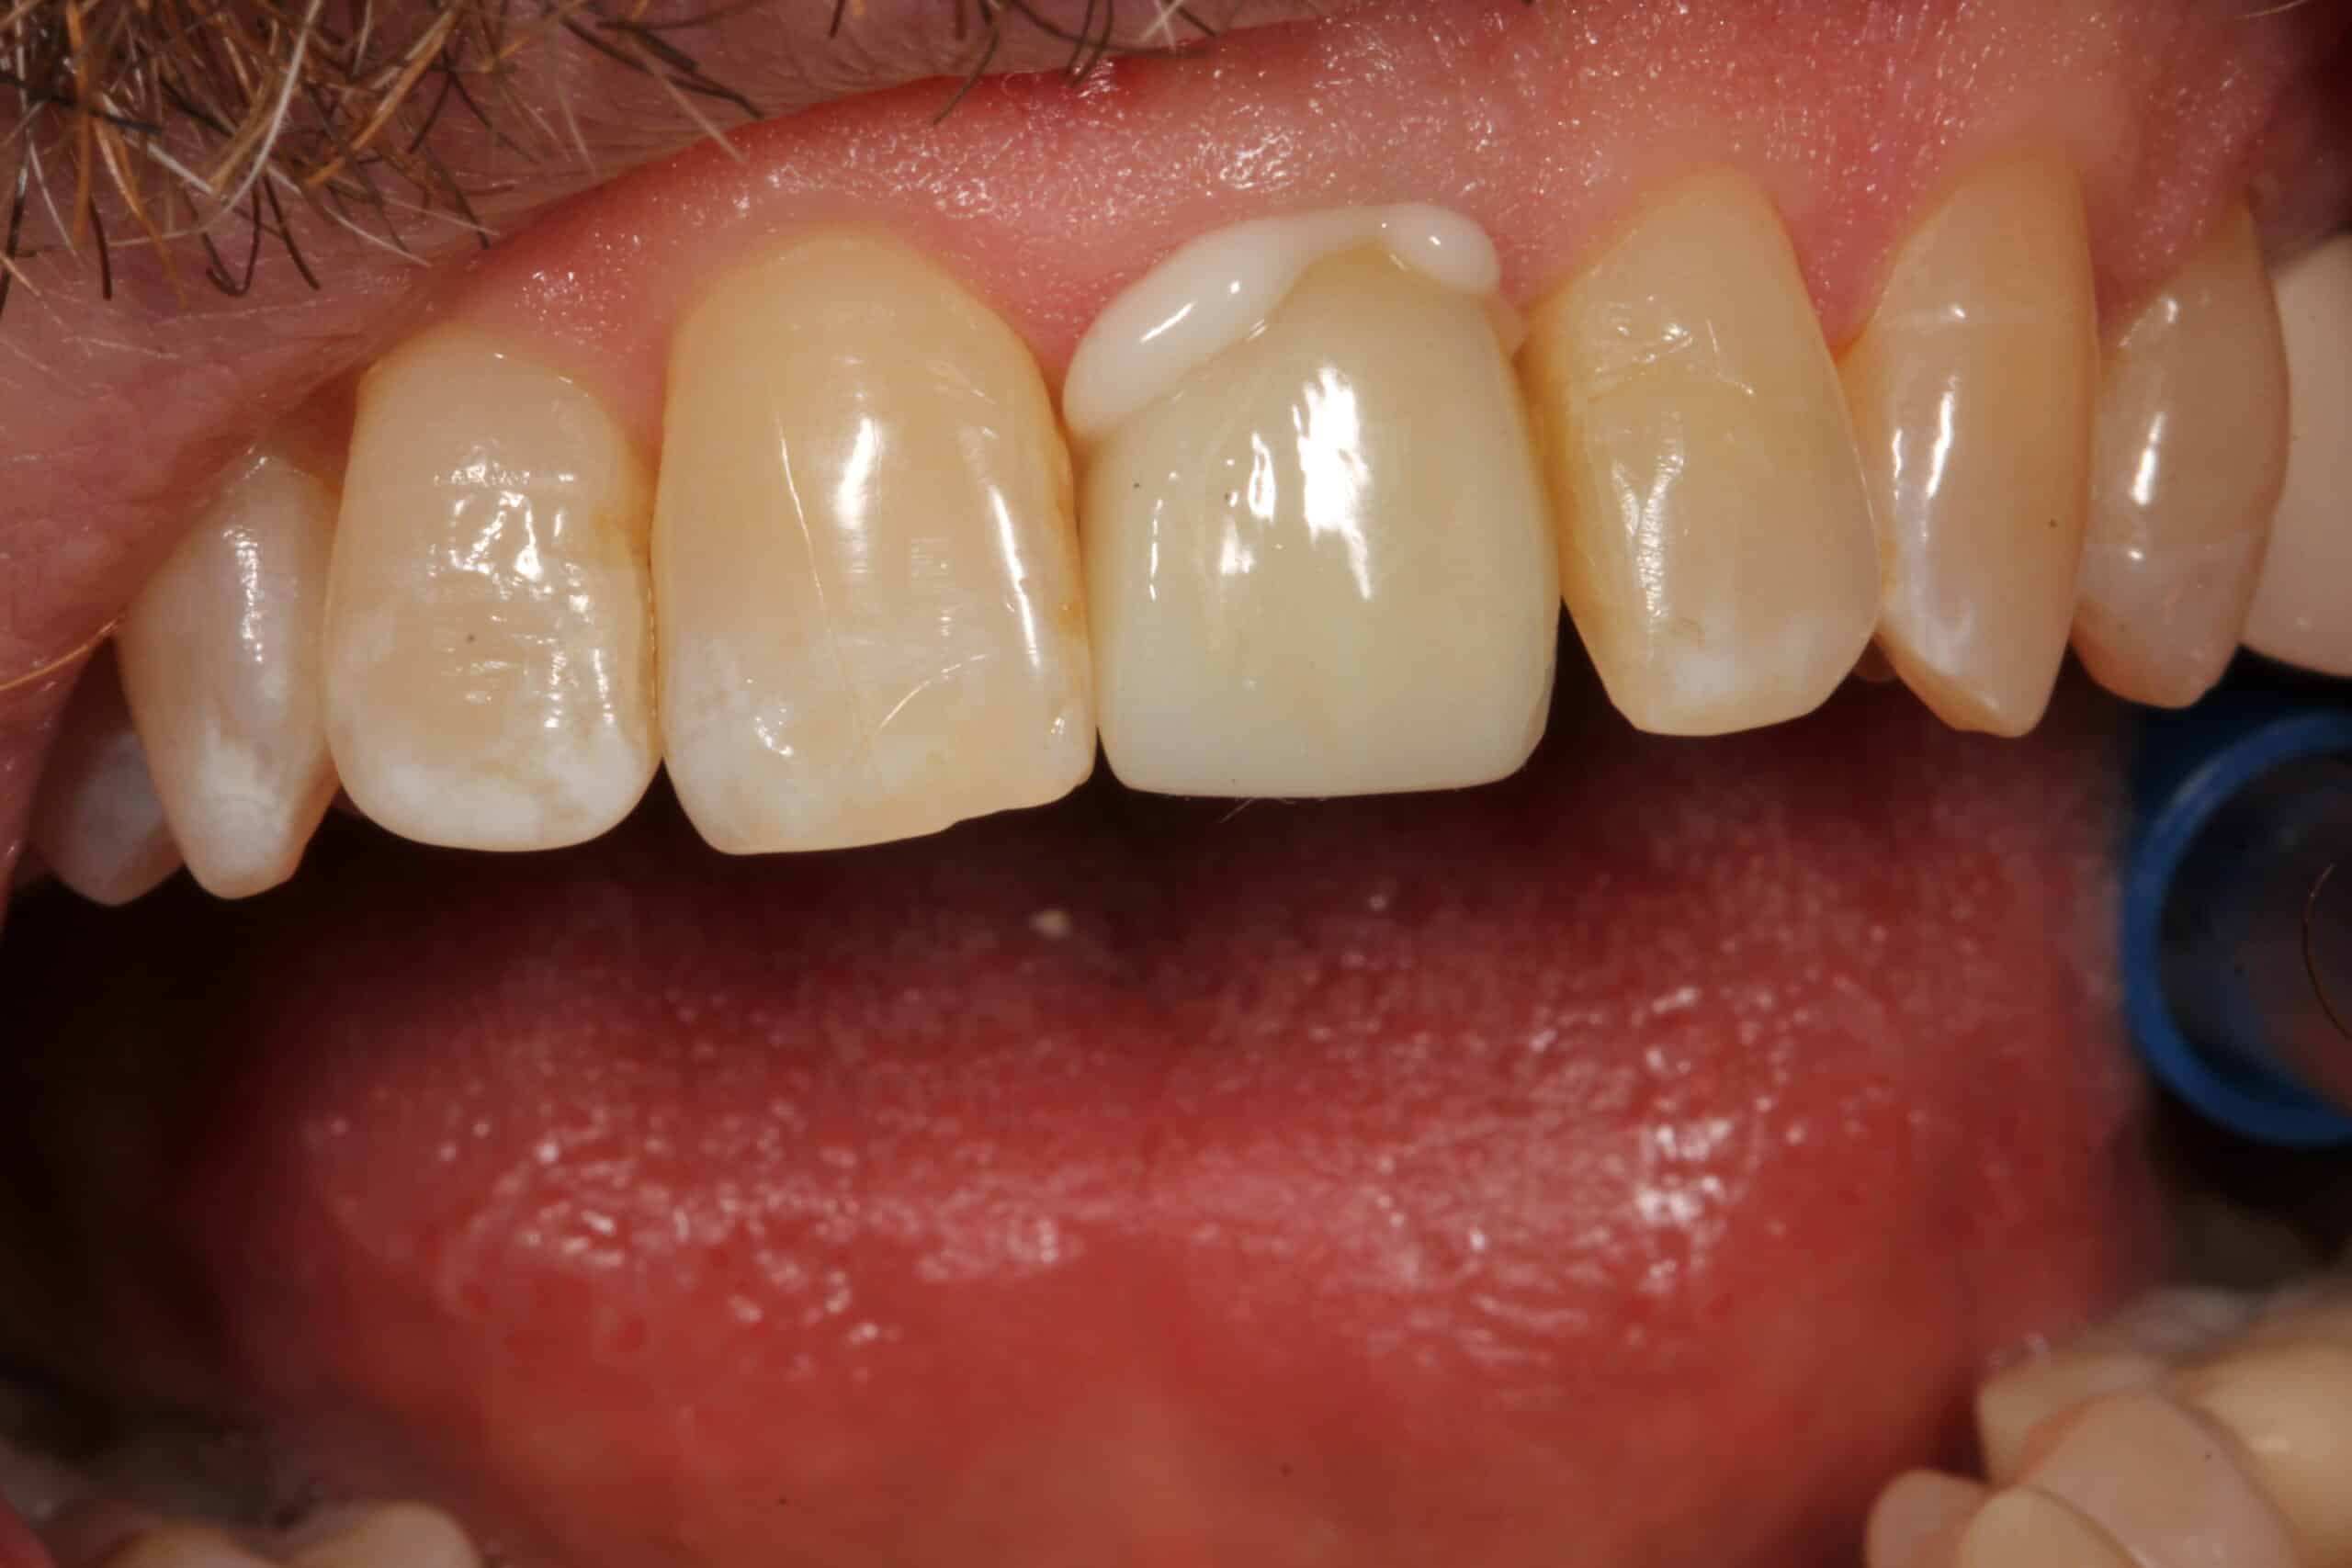

Tooth extraction for a cracked tooth

Not all Cracked or fractured teeth require to be extracted.  At Smile Arts of NY we can save teeth that maybe fractured or broken.  Our dentist will carefully evaluate the condition of your tooth or teeth.   Many fractured teeth can be saved with a crown or a filling.  We may have to do a little work on your gums with our small diode laser. if the tooth fractured under your gum.  A root canal maybe necessary if there’s nerve damage to the tooth.